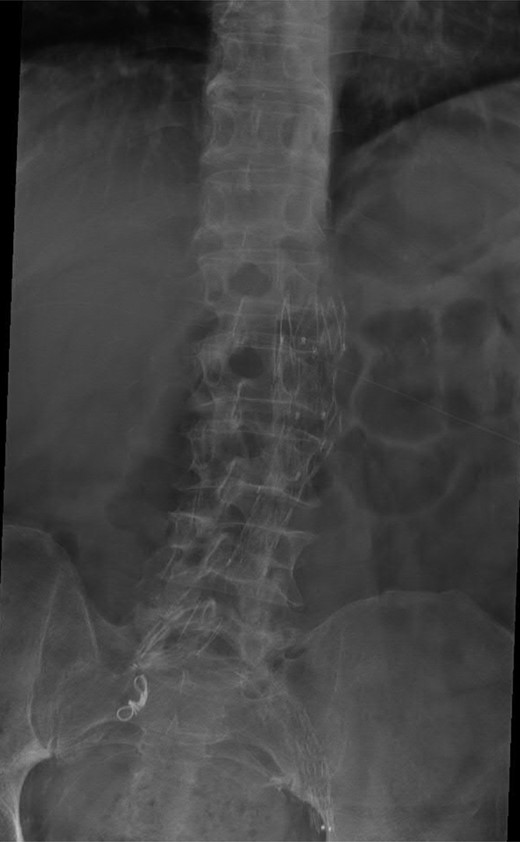

A 74-year-old male was admitted with an intracapsular fractured left neck of femur (Fig. 1). According to the NICE guidelines, he received a cemented THR (Fig. 2) via the posterior approach in the lateral decubitus position. Five weeks prior, he had an EVAR for a leaking AAA. Due to a calcified, narrow right common iliac artery (CIA), the EVAR consisted of a left aortouniiliac endograft with coil embolization of the right CIA and a femoro-femoral crossover graft (Figs 3 and 4).

Lateral radiograph of the lumbar spine demonstrating the aortouniiliac EVAR with coil embolization of the right CIA.